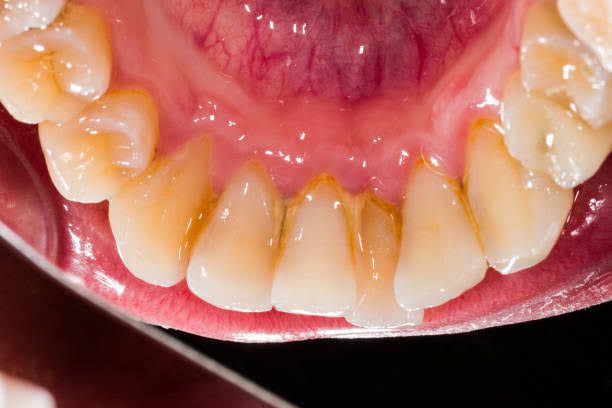

Tooth plaque forms when bacteria in your mouth mix with sugary or starchy foods like milk, juice, soft drinks, bread, pasta and fruit. These bacteria release acids that break down carbohydrates in food and drinks. If you don’t brush your teeth soon after eating or drinking, the combination of bacteria, acids and carbohydrates can mix into a sticky, colorless film called plaque.